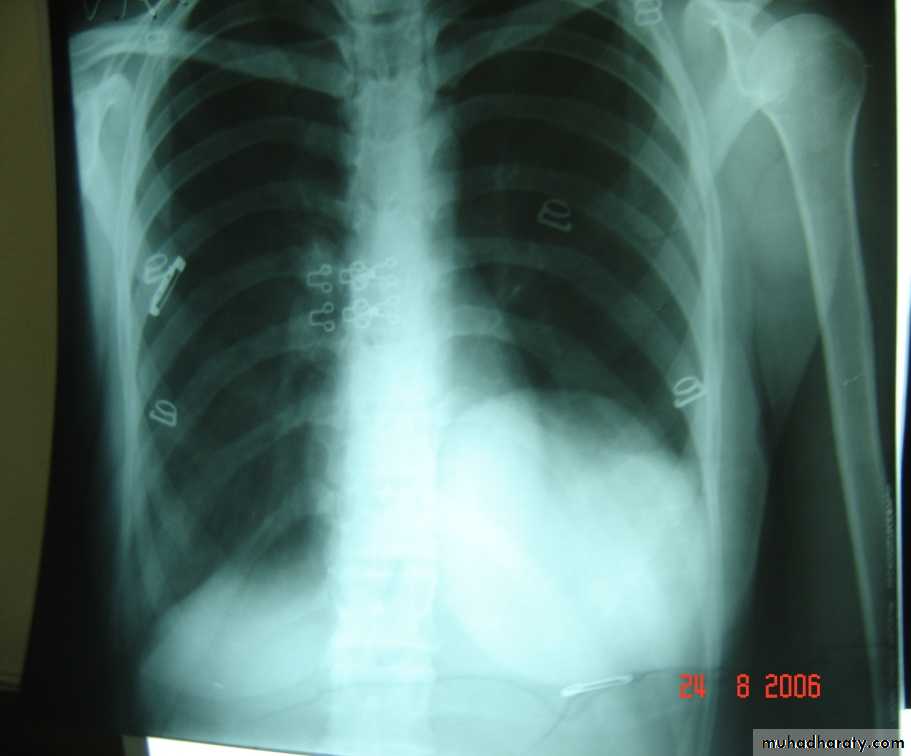

• 4-Pleural effusion

• Is the accumulation of fluid in the pleural space excessive transudation or exudation of the interstitial fluid from the pleural surface. It is signify pleural or systemic disease .

• Its effect depends on its size (mild , moderate or massive ) & the state of the underlying lung .It is classified as transudate when the protein content is less than 3g% or exudates when protein content is more than 3 gm % .Clinically patients will present with dyspnea & pleuritic chest pain

• Radio logically (concave meniscus sign)

• Treatment :-1-aspiration (thoracentesis) 2-tube thoracostomy